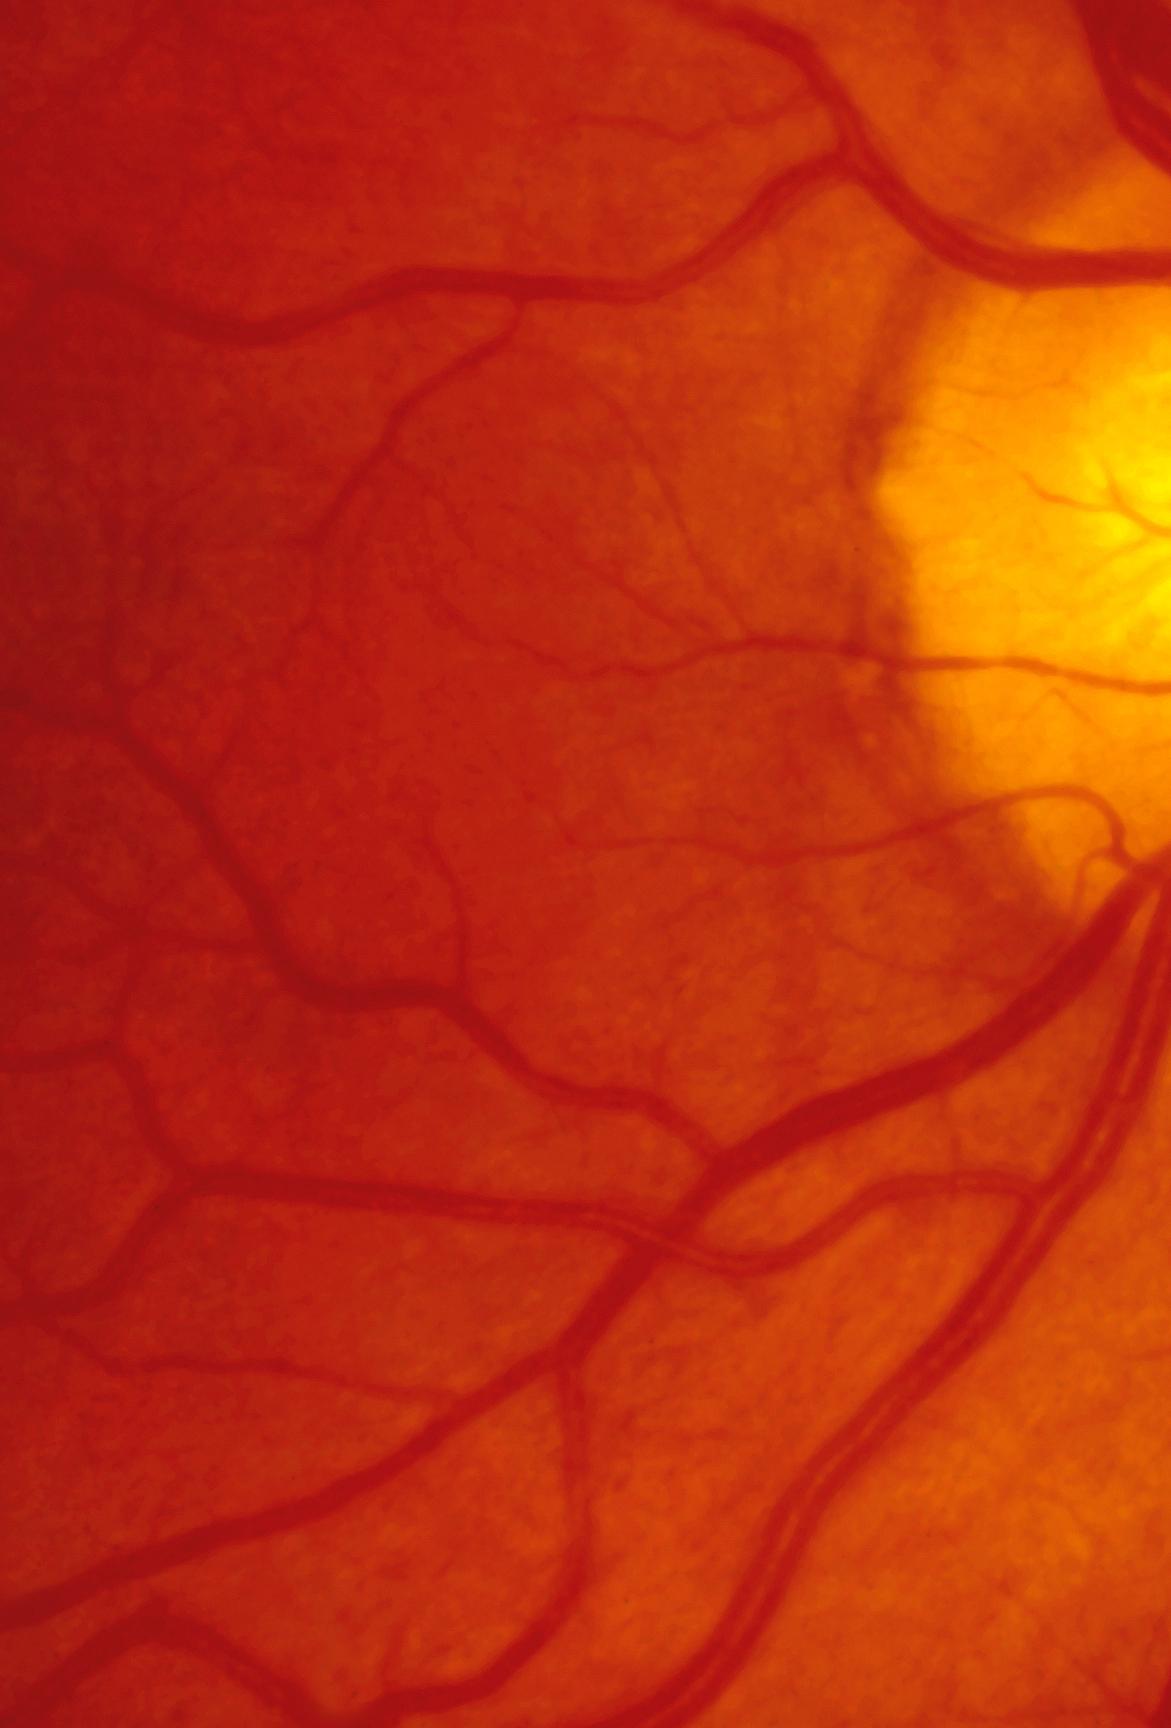

Los riñones son órganos sofisticados que desempeñan un papel fundamental en el adecuado funcionamiento del cuerpo. Los riñones filtran en el ser humano hasta 180 litros de sangre al día y reciben aproximadamente el 20% de la sangre que bombea el corazón en cada latido.

La filtración renal de la sangre elimina productos de degradación del metabolismo (por ejemplo; urea, amoniaco, la bilis del hígado, entre otros) en forma de orina, y controla los niveles de agua, electrólitos y pH de los líquidos corporales. Además, los riñones regulan la presión arterial, la producción de globulos rojos, la activación de la vitamina D y evitan la pérdida de proteínas por la orina.